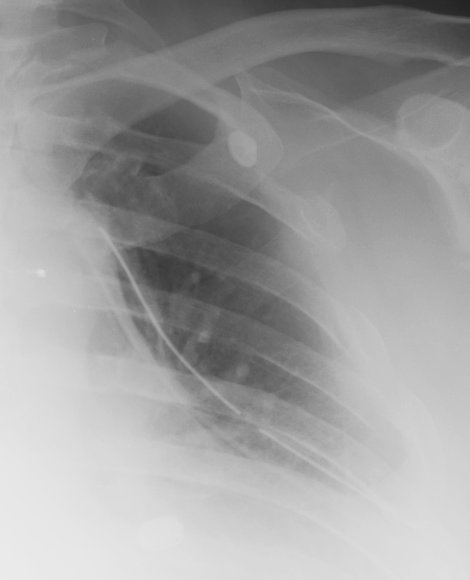

- Click on the image for a larger versionBAxial CT. This image is acquired through the shoulder and shows a comminuted fracture of the glenoid as well as one of the rib fractures identified in the chest radiograph.